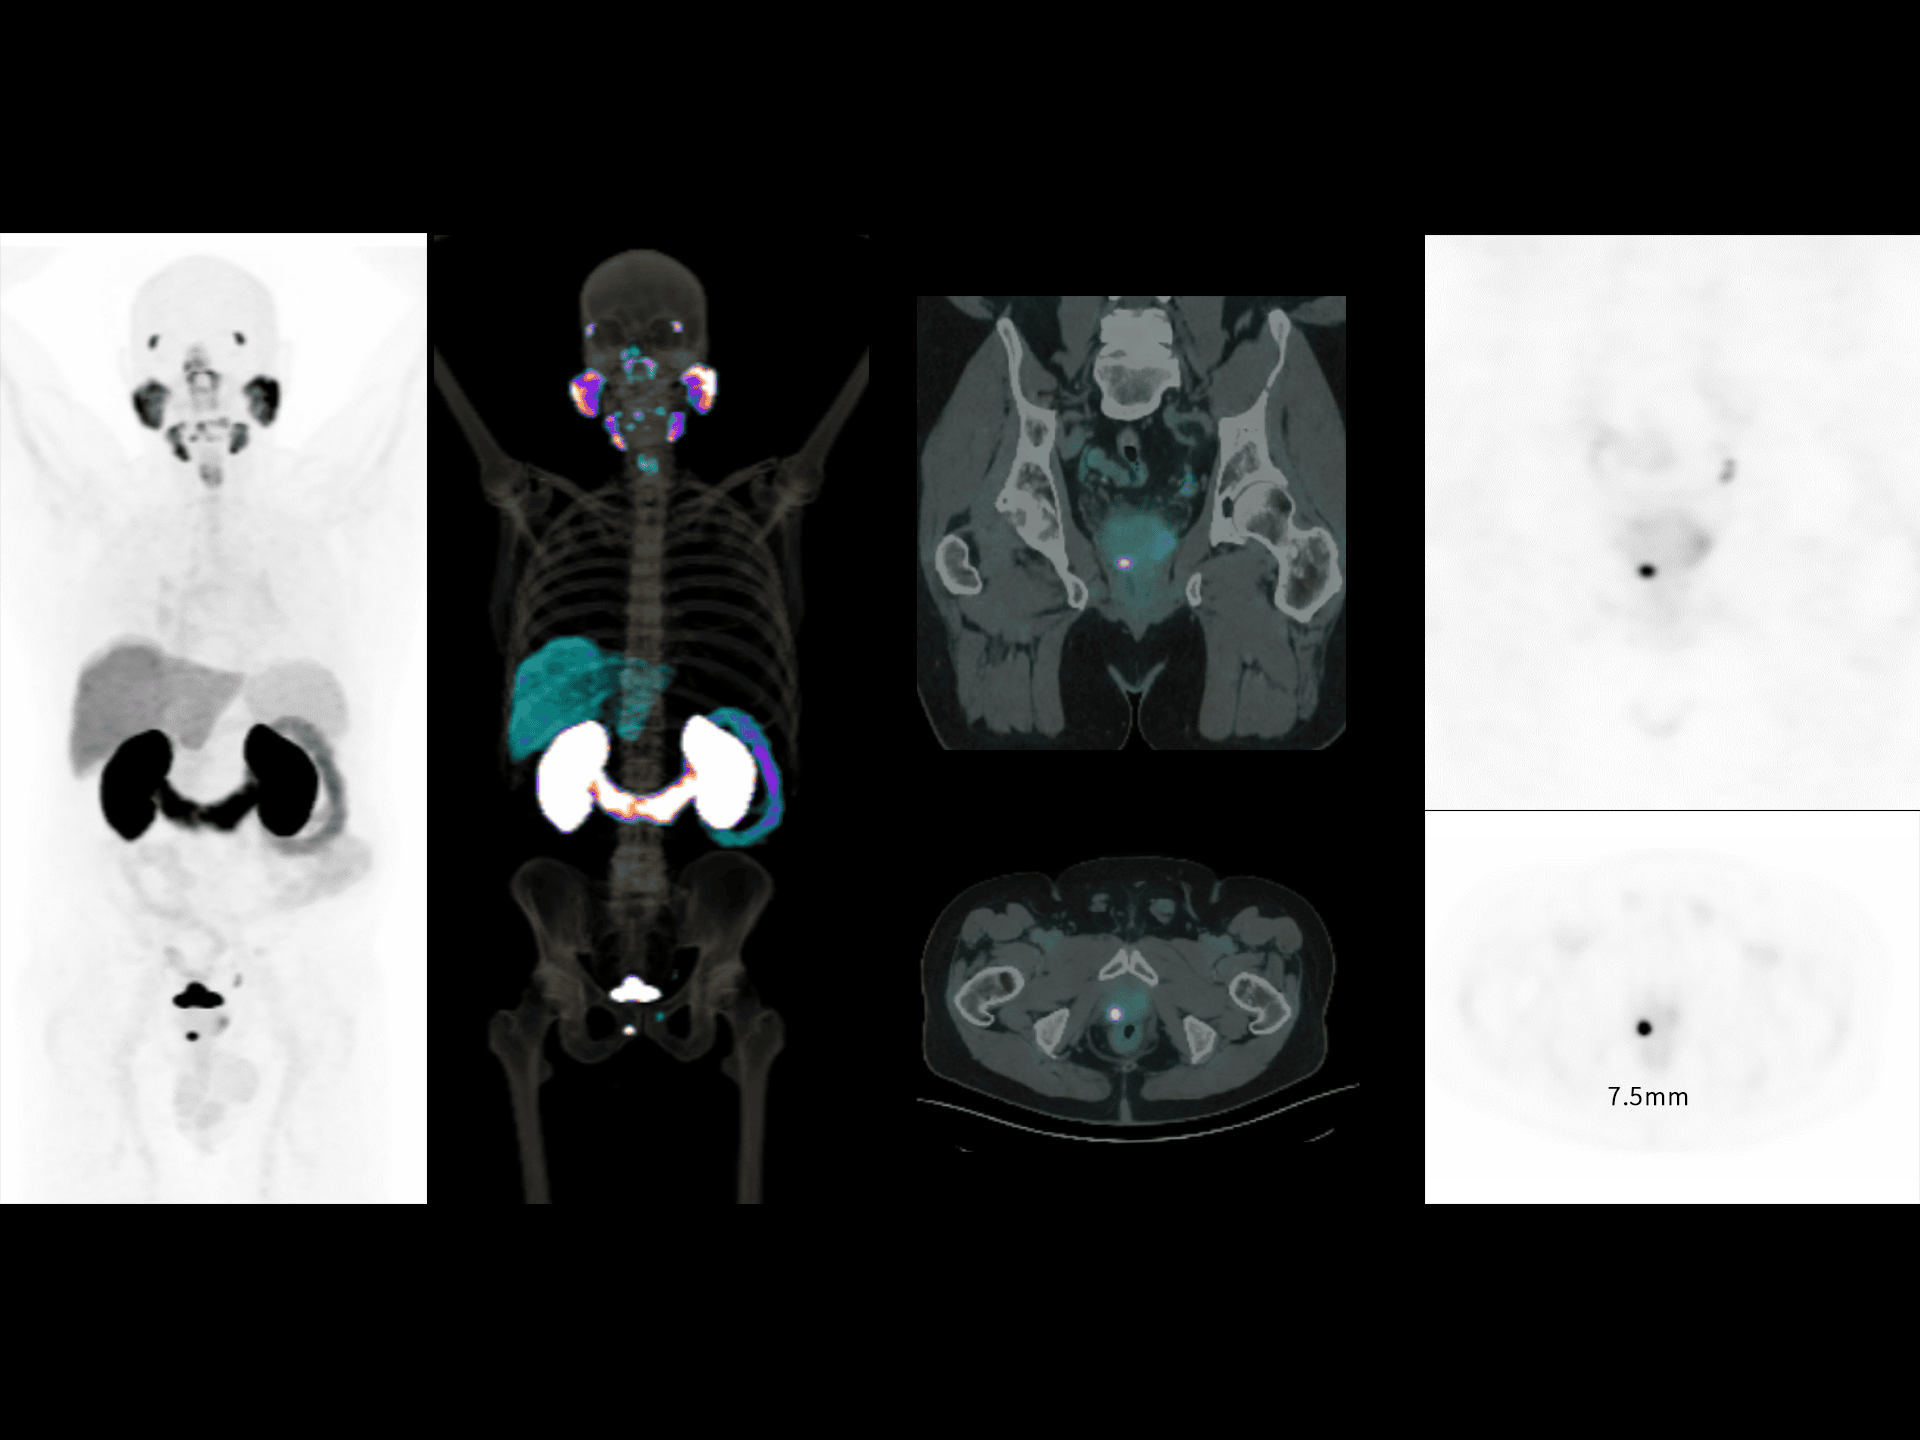

Vizualizare clară a leziunilor în imagistica 68Ga-PSMA

Detectare precisă și contrast superior pentru leziuni în scanările cu radiotrasor 68Ga-PSMA.